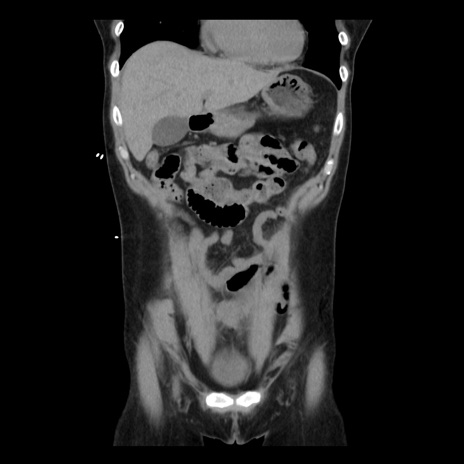

横断像

矢状断像